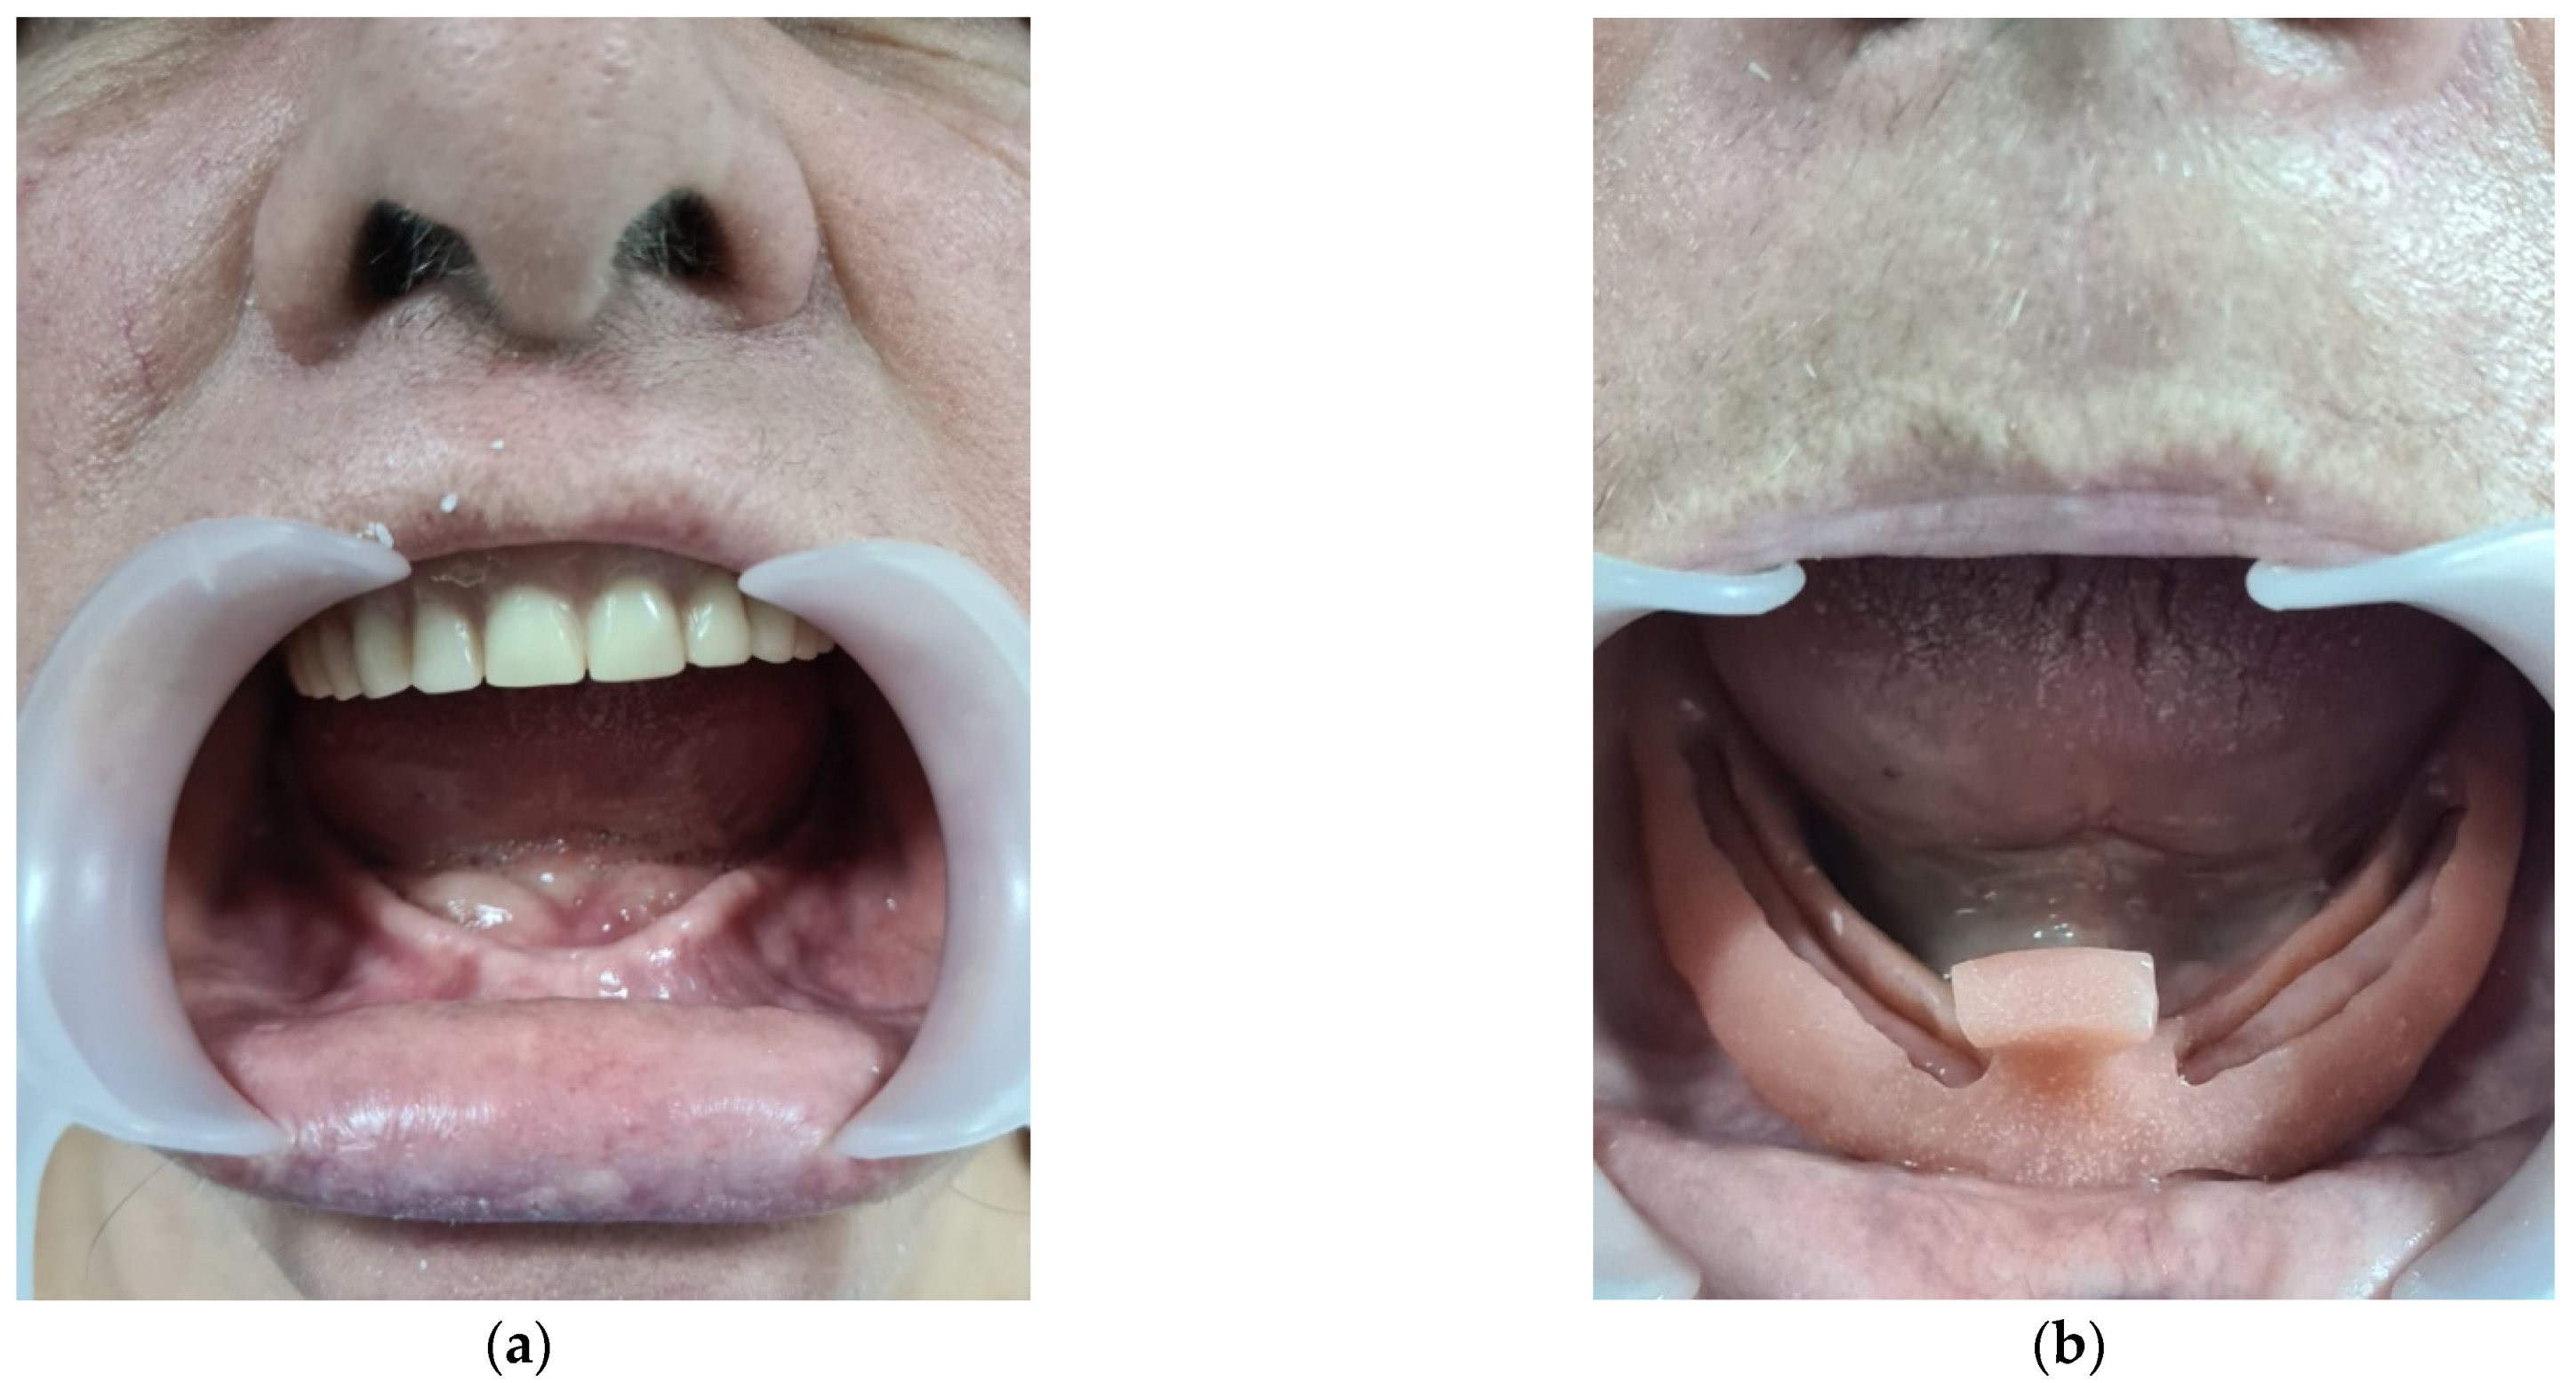

3.1. CASE REPORT 1